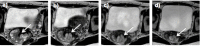

CT-based radiotherapy workflow is limited by poor soft tissue definition in the pelvis and reliance on rigid registration methods. Current image-guided radiotherapy and adaptive radiotherapy models therefore have limited ability to improve clinical outcomes. The advent of MRI-guided radiotherapy solutions provides the opportunity to overcome these limitations with the potential to deliver online real-time MRI-based plan adaptation on a daily basis, a true "plan of the day." This review describes the application of MRI guided radiotherapy in two pelvic tumour sites likely to benefit from this approach.